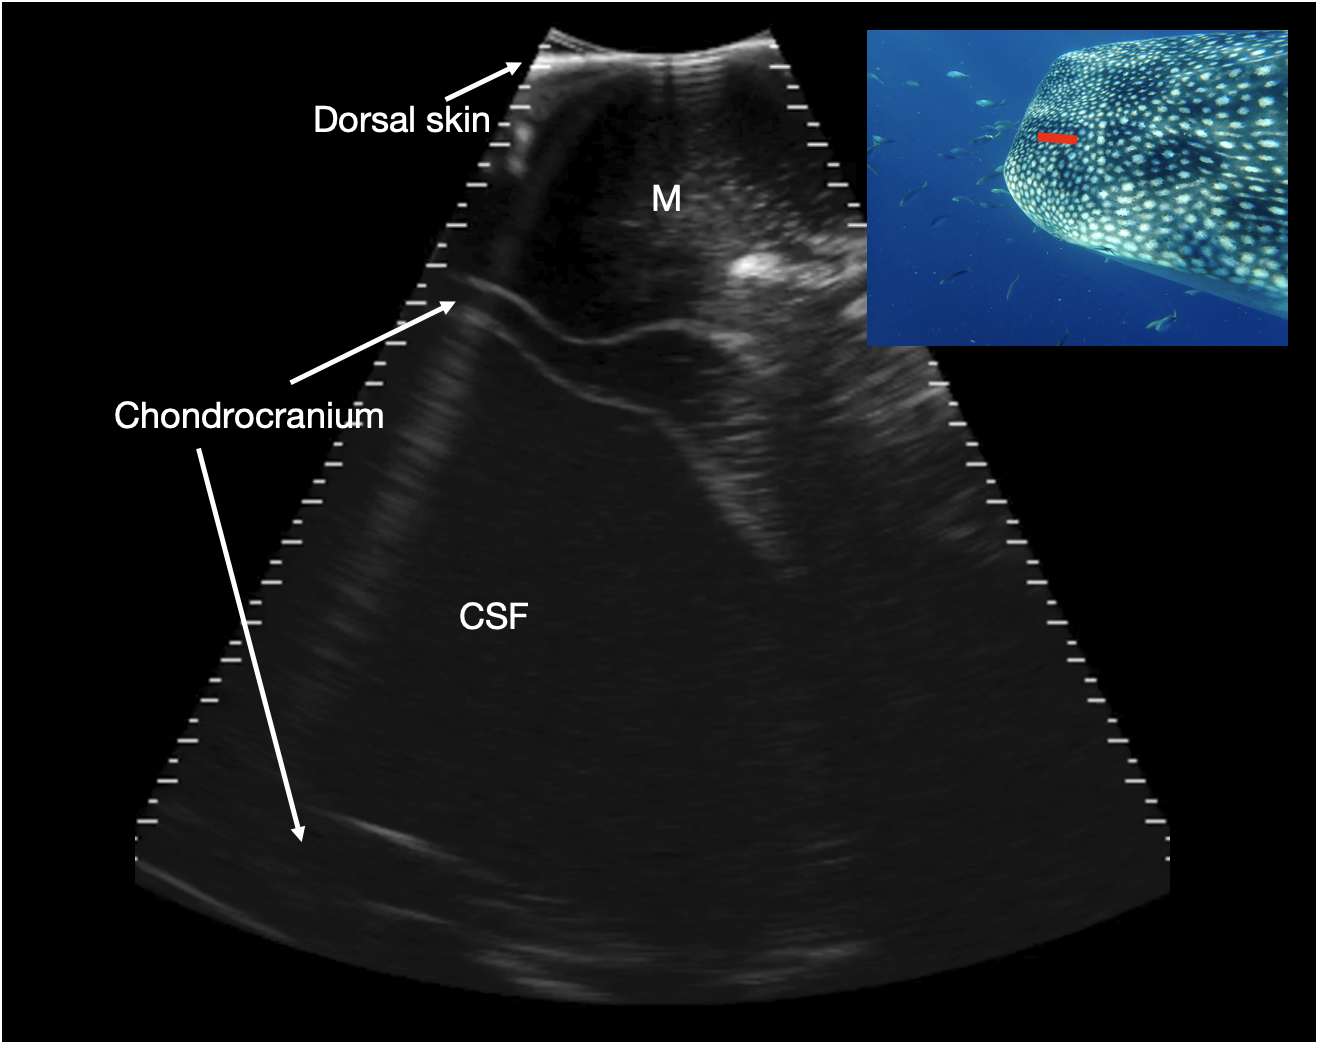

Figure 9

Parasagittal neurocranium. Slightly paramedian sagittal sonogram of mid dorsal calvarium. The image is oriented with rostral to the left of the image. A large, fluid filled cavity is present deep to the dorsal musculature and surrounded by chondrocranium (marked CSF), at a depth between 7 and 11 cm. This is thought to correspond to a large cavity that contains cerebrospinal fluid (CSF), extending rostrally from the brain into the rostral dorsal head. Photograph insert shows dorsal view of a whale shark head and approximate transducer position in red. Photo credit Lucy Armstrong.